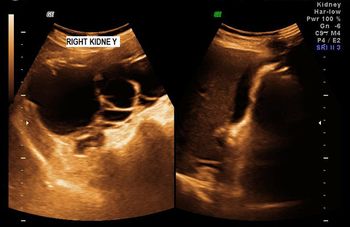

A 78-year-old patient presented with history of hypertension and renal failure.